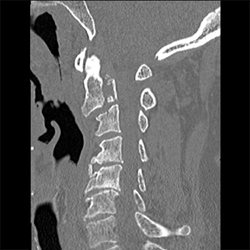

Cervical Spine Trauma Case 09